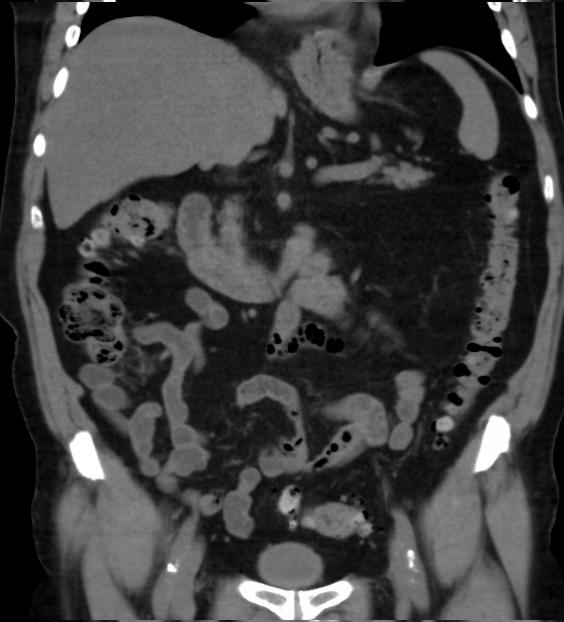

Aspect TDM du tuberculose ileocaecale est : Epaissisement

circumferentiel de la paroi ileum et caecum . Asymetrique

epaissisement de la valve ileocaecale .Mesenteric

lymphadenopathie et tuberculose pulmonaire est le plus

souvent .

Tuberculose ileocaecale avec image de

deformation du caecum . Epaissisement asymetrique du

caecum avec image de lymphadenopathie

mesenterique . TDM en coupe axiale |

Image TDM en coupe axiale :

Epaississement de la paroi de ileon . Lymphadenopathie peut se voyait sur cette

coupe |